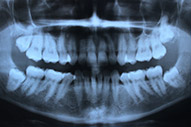

Roentgen

Röntgen

Röntgen ist nach wie vor ein wichtiger Bestandteil zahnärztlicher Diagnostik. Unser Artikel informiert über die Anwendung und Funktionsweise analoger und digitaler Technik.